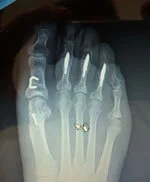

Before - 1st MTPJ fusion

After - 1st MTPJ fusion